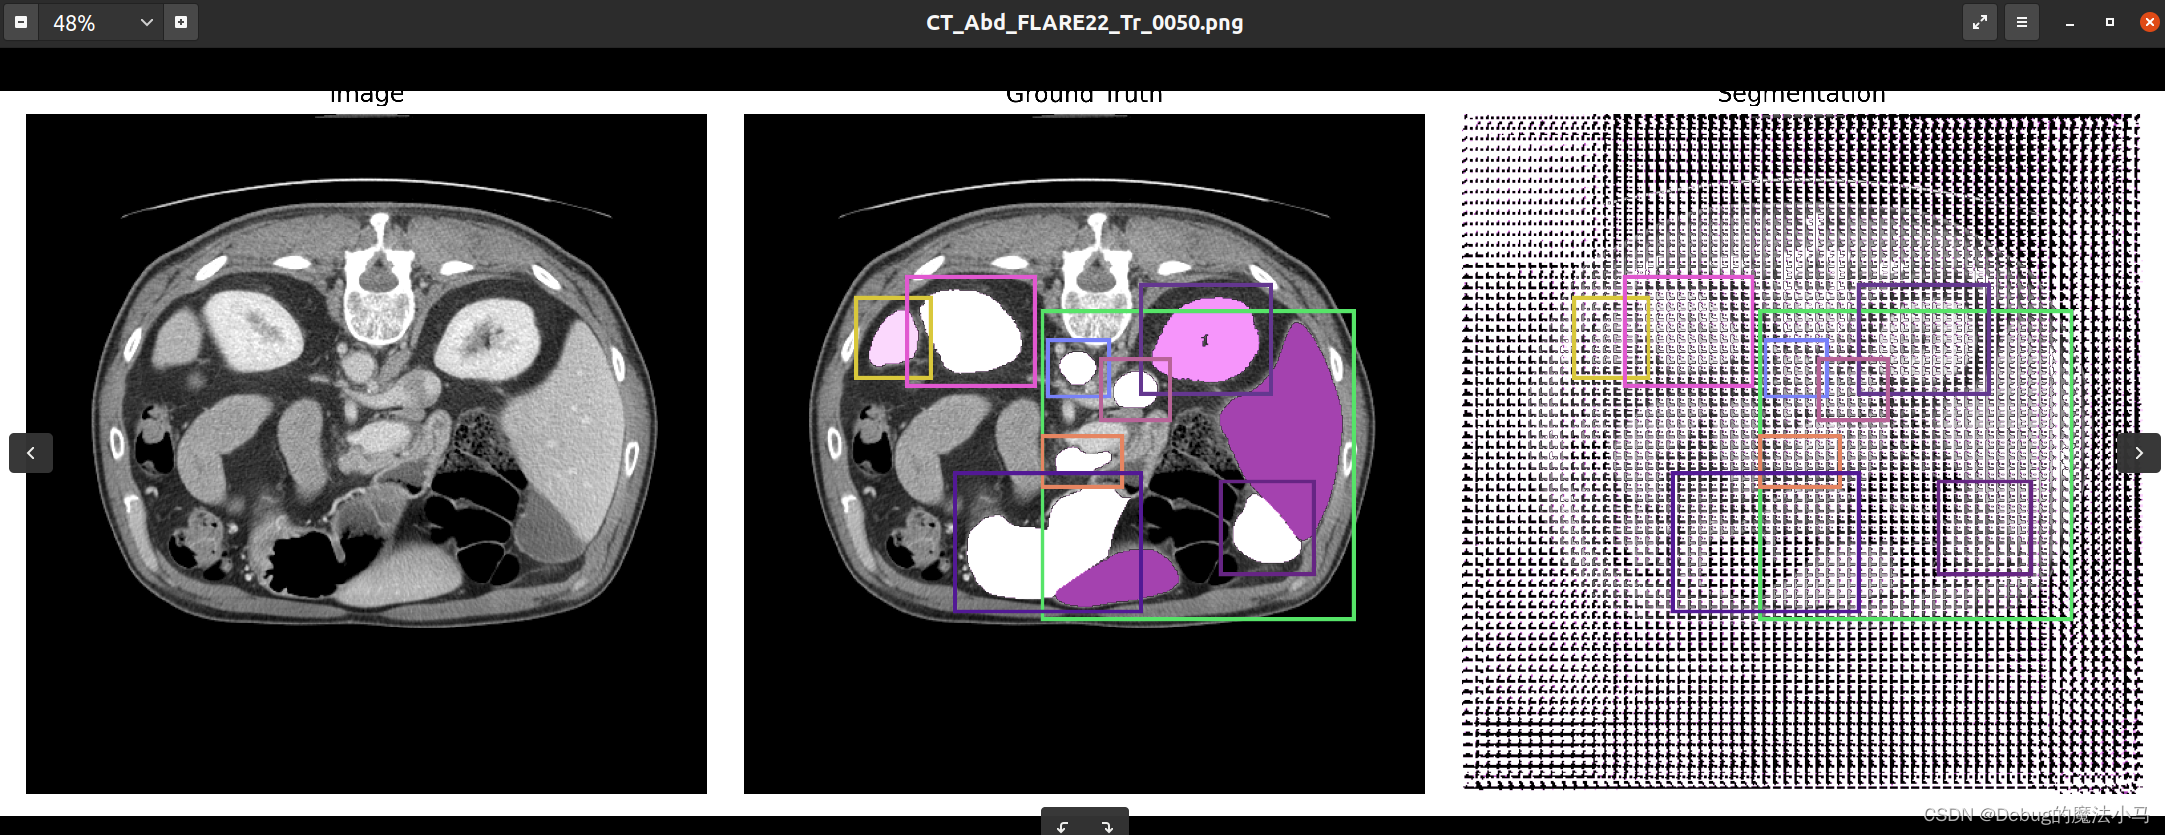

测试一下:

这是之前的结果图:

我把save_overlay参数设为True,运行后:

似乎没啥问题。暂时先这样了。